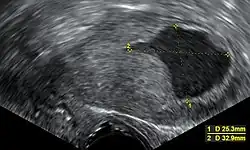

Transvaginal ultrasonography showing a uterine fluid accumulation in a postmenopausal woman